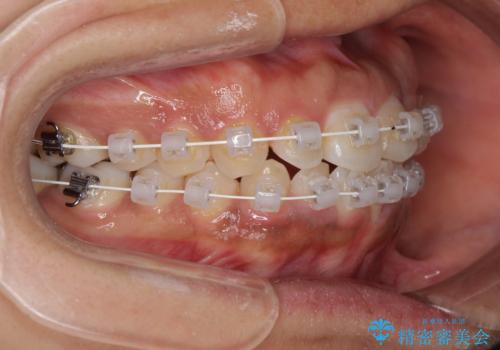

- インビザライン・審美装置

当初はインビザラインにて治療を開始しましたが、自己管理による治療が難しくなり、ワイヤー矯正へ転換して継続しました。

2年ほどインビザライン矯正を続けましたが、終了することができず、ワイヤーへ転換後は1年弱で終えることができました。